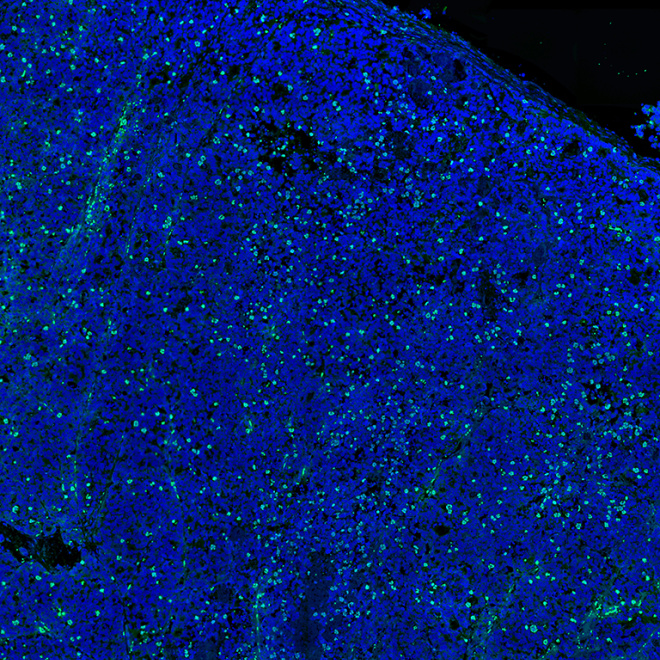

Koch Institute researchers develop new strategies to pinpoint cancer’s vulnerabilities and overcome resistance. Explore selected projects through the images below.